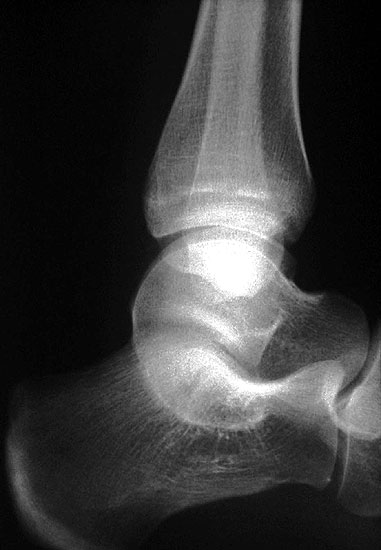

Z.n. Distorsion des Fußes mit „Ruptur“ der (vorbestehenden) talocalcanearen Coalitio. Die Wassereinlagerung in den an die Coalitio angrenzenden knöchernen Bezirken ist im MRT gut zu erkennen. Nach monatelangen Beschwerden spontane Besserung.

Abbildung 1

• Anhaltende Schmerzen nach vermeintlichen oder tatsächlichen Distorsionen („Aktivierung“ der Coalitio, vgl. Abb. 1)